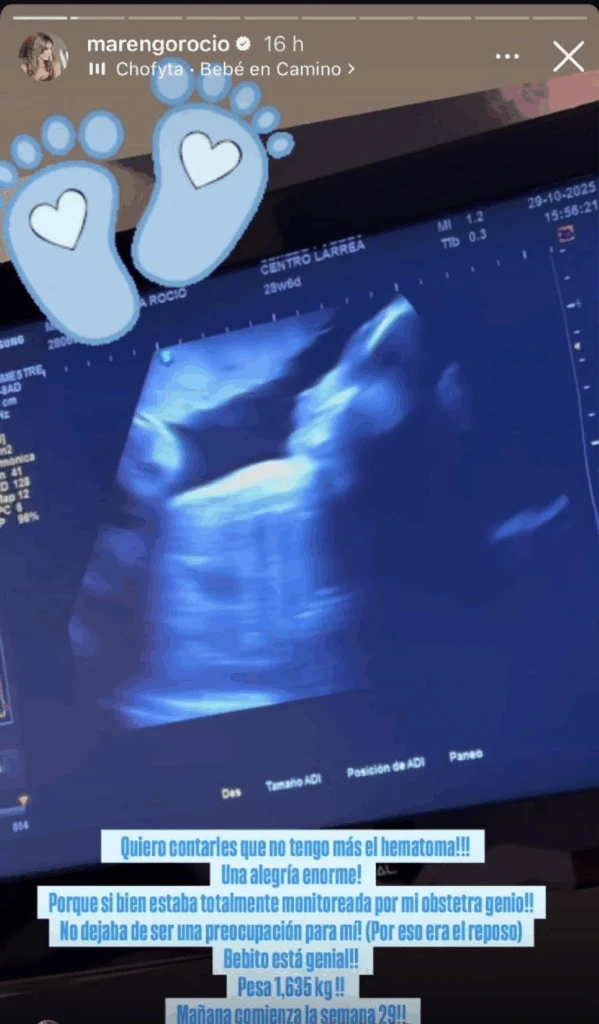

Como toda etapa previa de maternidad, en la gestación del bebé pueden acontecer inesperados escenarios pero que forman parte del proceso. En el caso de Rocío la aparición de un hematoma encendió las alarmas.

“Me asusté porque me dieron un pequeño reposo, ¿viste? Por un hematoma. Listo. Entonces, bueno, a cada rato le pregunto a Bebito: ‘Bebito, dame una señal, decime que estás bien’. Pa pa, patea”, llegó a decir Rocío.

Exponiendo detalles de lo que pasó, la mediática expuso: «Bebito está solito en la panza, ya no tiene el maldito hematoma que me hizo estar re nerviosa estos días. Fueron casi dos meses así, un día se achicaba y al otro se agrandaba».

Al momento de contar más sobre lo que pasó, pese a que pudo haberse sometido a un procedimiento, todo ocurrió de forma natural. De todas formas, este antecedente será algo a tener en cuenta de cara a los meses que restan.

“Se podía absorber el hematoma, pero en mi caso lo expulsé, sí, como escuchan, es la realidad, fue una porquería pero sucedió. Estuve varios días de reposo absoluto y hoy en la ecografía ya no lo vieron. Igual, le quiero aclarar a mi entorno, que ya no voy a estar en reposo pero no voy a estar al palo, no voy a trabajar. Quedan dos meses para que nazca, a lo sumo iré un ratito al shopping y haré unas fotitos tranquilas para Instagram”, sentenció.